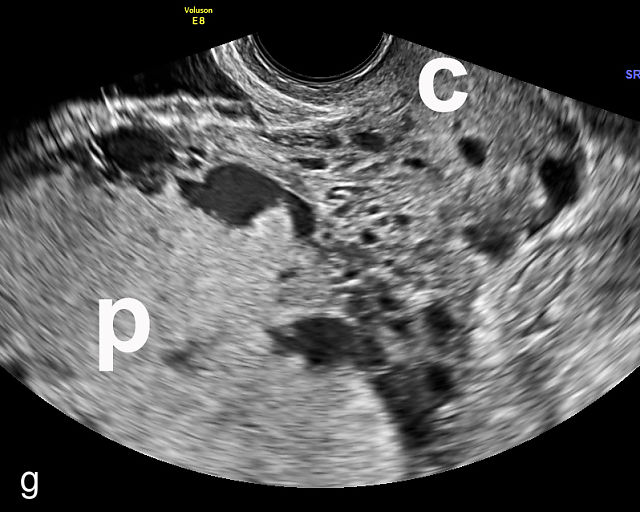

Placenta previa and low-lying placenta. (a) Transabdominal grayscale ultrasound image suspicious for placenta previa. The placenta (PL) appears to overlie the internal cervical os (CX). Note the time stamp: 2:19:37. (b) Transvaginal ultrasound of the same patient taken approximately 50 minutes later. Note the time stamp: 3:10:25. The internal os and the lower placental edge are both clearly seen, and the placenta does not overlie the internal os. Because the lower placental edge is 1.93 cm from the internal os, it will likely resolve by the third trimester. (c) Transabdominal grayscale ultrasound of placenta previa. The placenta (p) covers the cervix, but the cervix, especially the internal os, cannot be visualized due to shadowing. (d) Transabdominal grayscale ultrasound of placenta previa. The placenta (p) covers the cervix (c) but shadowing obscures adequate visualization. The internal os is indicated by the arrow. (e) False-positive image of placenta previa on transabdominal grayscale ultrasound. The bladder (b) is full, pushing the anterior and posterior walls of the lower uterine segment (ls) together making it appear that the placenta (p) overlies the internal os of the cervix. In reality, the line depicted by the arrowheads is where the anterior and posterior walls of the lower segment are in proximity to each other. The cervix is much lower and is obscured by shadowing (c). (f) Transabdominal grayscale ultrasound image of placenta previa. The placenta (p) covers the cervix (c), but the cervix, especially the internal os, cannot be visualized due to shadowing. b, bladder. (g) Transvaginal grayscale ultrasound image of placenta previa. The placenta (p) completely covers the internal os (arrow) of the cervix (c). The internal os can be seen clearly. h, fetal head. (h) Transvaginal grayscale ultrasound image of posterior low-lying placenta (p). The lower placental edge is clearly seen and is 1.56 cm from the internal os (arrow) of the cervix (c). The placental edge and the internal os are clearly seen. h, fetal head. (i) Transvaginal grayscale ultrasound image of a posterior placenta previa (p). The internal cervical os is clearly seen (arrow). c, cervix. (j) Transvaginal grayscale ultrasound image of an anterior placenta previa (p). The internal cervical os is clearly seen (arrow). c, cervix; h, fetal head. (k) Transvaginal grayscale ultrasound image of a posterior placenta that was thought to be low-lying on transabdominal sonography but could not be adequately assessed. This examination clearly shows the lower edge of the placenta (p) to be 2.18 cm from the internal os (arrow) of the cervix, firmly establishing that the placenta is not low-lying and allowing the patient to undergo labor safely and deliver vaginally. c, cervix. (l) Transvaginal grayscale ultrasound image of placenta previa. The placenta (p) completely covers the internal os (arrow) of the cervix (c). The internal os can be seen clearly.

Most cases of placenta previa will be suspected prenatally by transabdominal ultrasound.49 However, this approach has several limitations and may be inaccurate.72,73,74 because the relationship between the placenta and the internal cervical os may be difficult to assess by transabdominal ultrasound.72,73,74 The bladder may be full, pushing the anterior and posterior walls of the lower uterine segment together, falsely creating the impression of a placenta previa (Figure 5e).61 There may be considerable shadowing, including by the fetal presenting part, which may limit the accuracy of transabdominal ultrasound (Figure 5d,f).75 Posterior placentas may be more difficult to assess.

Transvaginal ultrasound overcomes these limitations (Figure 5g–l).72,73,74,76 The probe is inserted into the vagina and therefore is closer to the region of interest.51,61 In addition, transvaginal transducers have higher frequencies and superior resolution compared to transabdominal transducers. Transvaginal ultrasound is safe and is not associated with increased bleeding.72,73,74,75,76 As such, transvaginal ultrasound should be the imaging modality of choice whenever there is suspicion of placenta previa.49,67,77